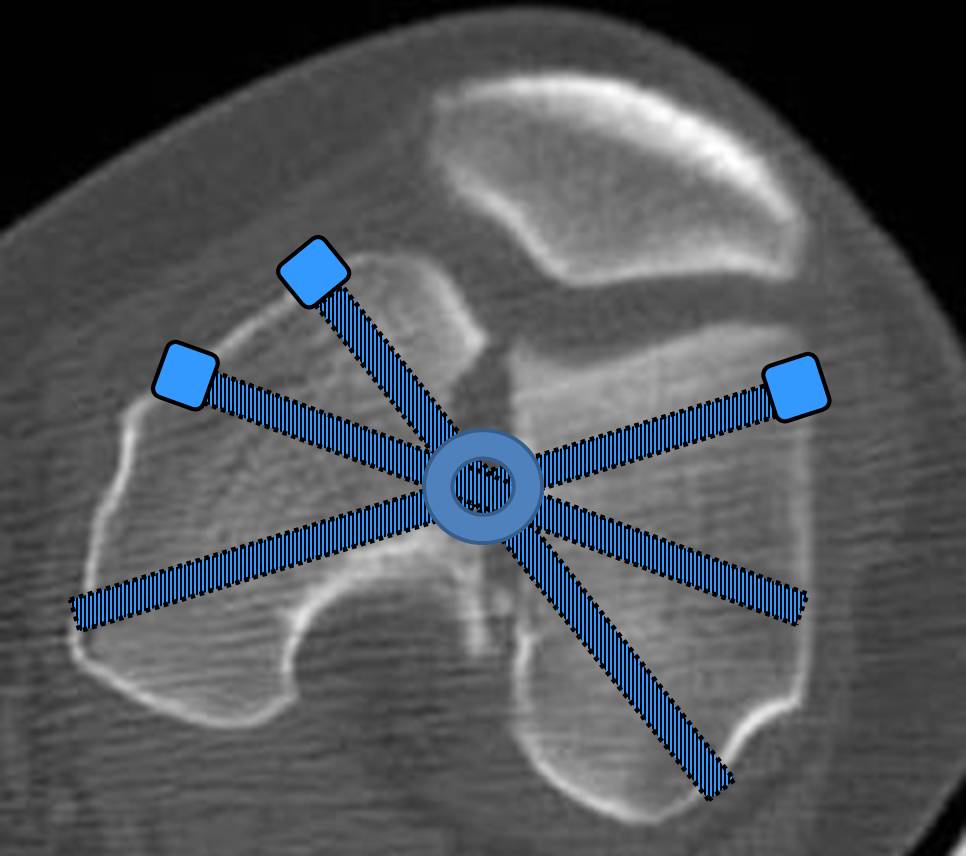

И уже лет шесть мы используем возможность ввести в дистальное овальное отверстие 3 винта, которые именно запираются в этом отверстии, не люфтят, а обеспечивают угловую стабильность - см картинку.

Получается и стабильно, и очень дистально, нижний край отверстия в 3 мм от дистального конца гвоздя.

С моей точки зрения, безусловная ценность предложенного Вами, Александр Николаевич, стержня состоит в возможности введения блокирующих винтов максимально близко к суставной поверхности дистального отломка, что значительно расширяет показания для применения интерлокинга. Можно предположить, что в техническом плане таким образом ввести блокирующие винты является непростой задачей. Кроме того, все они расположены в одной плоскости на небольшом расстоянии друг от друга.

Мне представляется, что конструкция с максимальными прочностными характеристиками будет иметь вид предложенной во вложенном файле. Такую конфигурацию расположения блокирующих отверстий на дистальном конце имеет стержень для большеберцовой кости фирмы ChM. Для бедренной кости такой стержень мне неизвестен. Поэтому в необходимых случаях (хорошо, что такие случаи встречаются не часто), как вариант, мы используем custom made стержень.

Наш гвоздик, выпускаемый предприятием ЦИТО, тоже скорее из универсальных, хотя и с расширенными возможностями для дистальных переломов. Это овальное отверстие внизу задумывалось как динамическое для высоких переломов, очень дистально его разместили, чтобы не опасаться перелома гвоздя по этому отверстию. А возможность вот такого введения винтов, образующих "сборный клинок", обнаружилась года через 3 его применения.